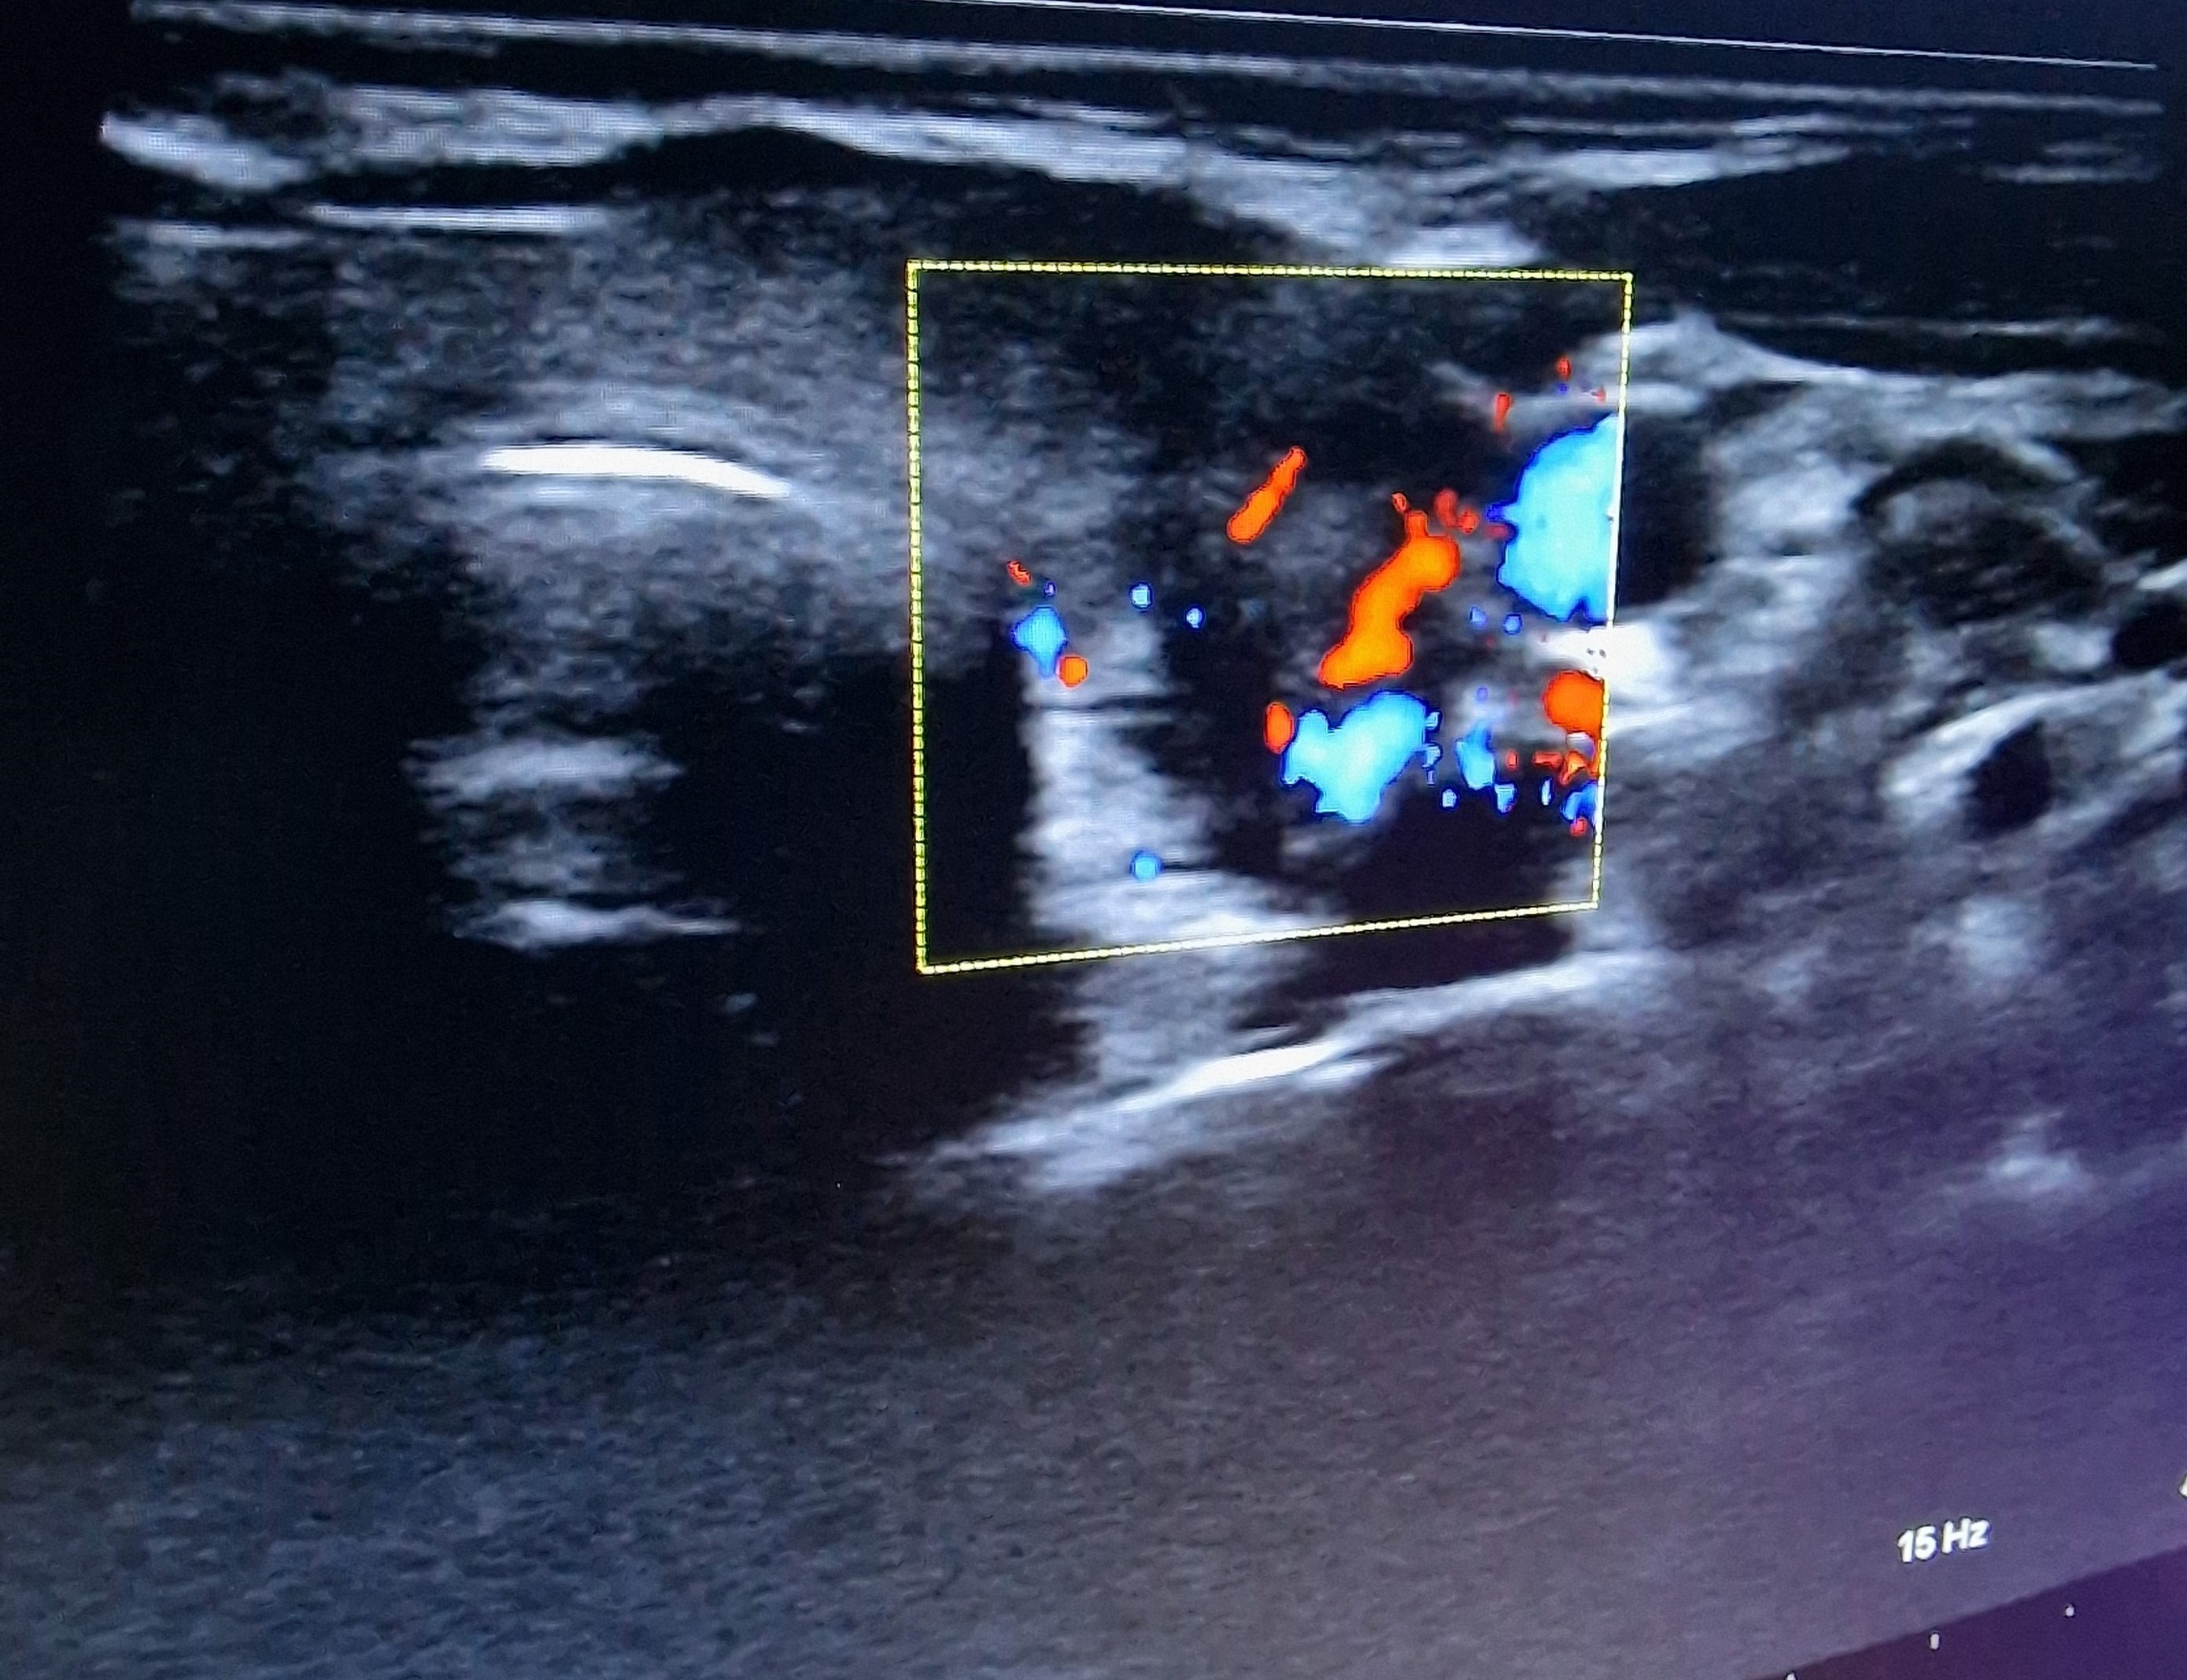

Ecografía cervical: tiroides de ecogenicidad heterogénea con áreas hipoecogénicas y ausencia de vascularización de éstas, Lóbulo Tiroideo Derecho 20 x 14 mm con nódulo < 10 mm no maligno e izquierdo 16 x 12 mm.

El diagnóstico diferencial se realizará con procesos infecciosos de vías respiratorias altas, con tiroidopatías con hipertiroidismo y ecogenicidad disminuida (enfermedad de Graves, patrón hipervascular; tiroiditis supurativa aguda), carcinoma tiroideo, hemorragia de nódulo tiroideo.